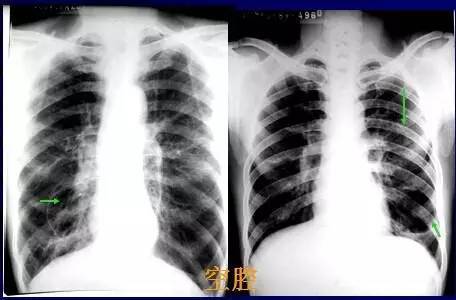

正常肺片x光图片,正常肺部CT

基础篇!肺部常见病变的x线片总结

正常胸片和肺炎胸片图